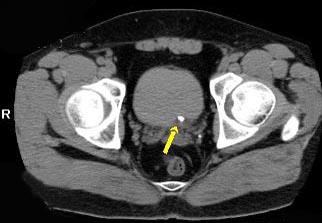

问题 男,29岁,下腹部疼痛不适伴血尿2 月,CT检查如图,下列说法错误的是 ( )

选项 A、考虑为盆腔静脉石 B、考虑为左输尿管下端结石 C、左侧输尿管扩张 D、左肾积水 E、左侧输尿管末端膀胱入口处可见一高密度影

答案 A